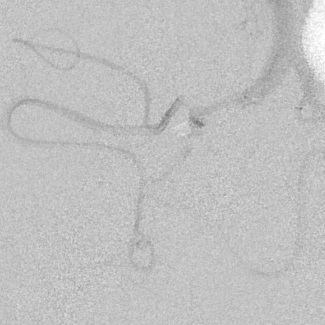

相逢就是缘,有求必全力以赴。立即进行全面评估,CTA和MRI发现颅内多发脑梗塞,脑干为重,双侧椎动脉颅内段基本看不到了,而进一步的DSA造影更为糟糕,左侧椎动脉的颅内颅外段直接全程完全闭塞,右侧颅外剩下一个小尾巴在血液中摇摇欲坠……,诺大的后循环仅仅靠纤细的后交通动脉从前循环借点血液过来,勉强续命,仅仅靠这点前循环的救急,可谓“杯水车薪”,不是“长久之计”,于是决定开通右侧闭塞的椎动脉(颅内+颅外,主要集中在V3+V4段)。

开通这么长节段的夹层所致的椎动脉,说说可以,做起来绝非易事,特别是颅内段,一旦跑到血管外出血,接近脑干,后果严重,谨慎开通的过程还算顺利,微导管带过就是磕磕绊绊不顺利,好吧,小球囊从上到下扩下来,不通,更换稍大球囊扩下来,还是不通,这夹层和狭窄不一样啊,支架导管带过仍然磕磕绊绊,不顺畅,铺开第一个支架,直接来了末端打开不良……,这么长的闭塞段,那得需要多少支架啊?万一放完了,钱花了,不通咋办?